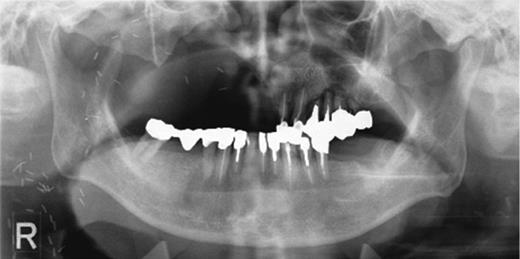

After sinus-lift surgery, marked swelling is obvious from the left buccal region to the angulus oculi medialis.